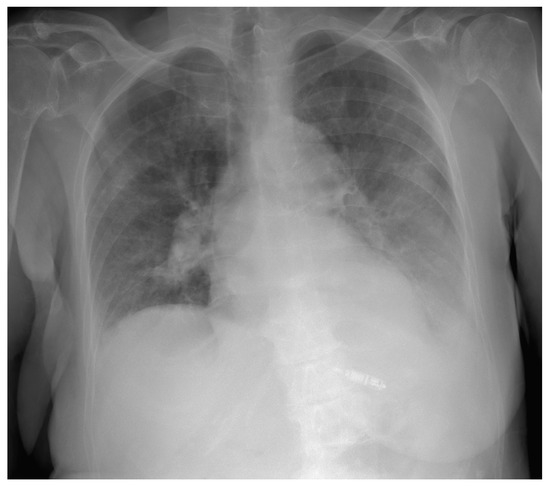

2. Case Presentation